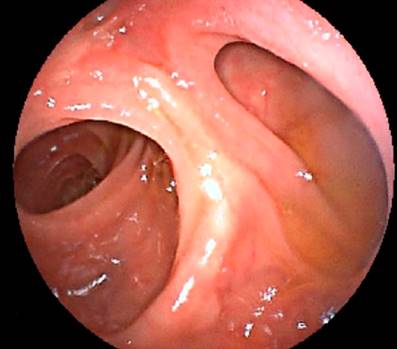

Paciente bajo anestesia general, en decúbito supino. Se introduce un EDB corto por vía oral, Fujifilm EI-580BT (longitud de trabajo 155 centímetros, diámetro distal de 9,4 milímetros y diámetro en la porción flexible de 9,3 milímetros, con un canal de trabajo de 3,2 milímetros y sobretubo de 95 centímetros). Se observa una anastomosis esófago-yeyunal normal y se avanza por el yeyuno hasta la anastomosis yeyuno-yeyunal (ubicada a 50 centímetros de la anastomosis esófago-yeyunal) (Figura 2).

Se ingresa por el asa biliopancreática (con ayuda de la fluoroscopia) hasta el muñón duodenal (aproximadamente 150 centímetros de longitud) (Figura 3). Se identifica la papila duodenal de aspecto normal (en el cuadrante superior) (Figura 4). Se intenta la canulación con catéter punta cónica, con papilótomo de arco y con papilótomo de aguja, pero no es posible avanzar la guía hacia la vía biliar, por lo que se utiliza un papilótomo invertido; se logra avanzar la guía hidrofílica hacia la vía biliar (Figura 5).